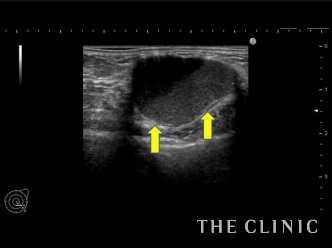

ただ、術前の触診で7個のしこりが認められ、さらにエコー検査では20個以上のしこり見つかりました。大きいものだと4cm以上ものも。そのため、しこり除去の処置をご提案しました。

この方のしこりは吸引針で穿刺するだけの処置で除去することができるものでした。ただし、触診では確実にしこりに吸引針を刺すことが困難です。そのため、このようにリアルタイムで映し出されるエコー画像を確認しながら、しこりに吸引針を挿入し、オイルとなった脂肪を吸い出していきます。